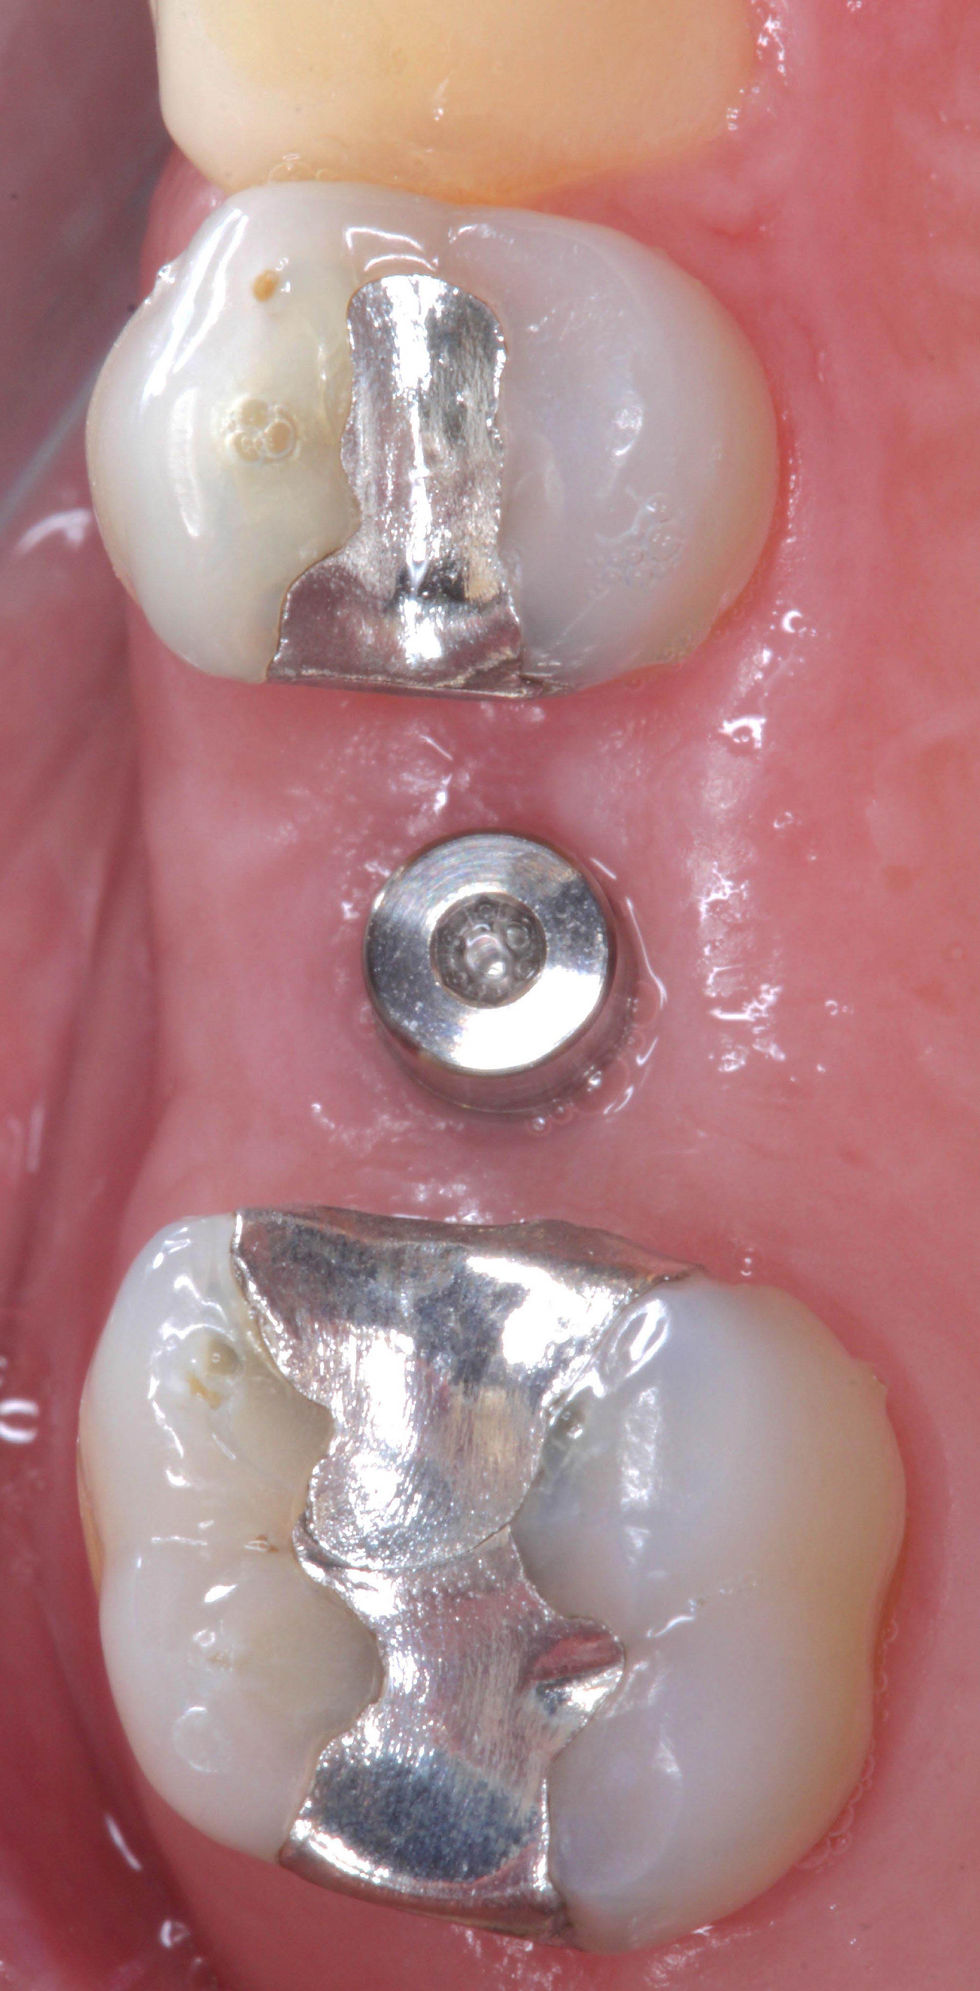

4 months after the surgery, the site is open to take the final impression: the excellent healing of peri-implant soft tissue can be appreciated.

After 4 months from the surgery, the final crown is delivered.